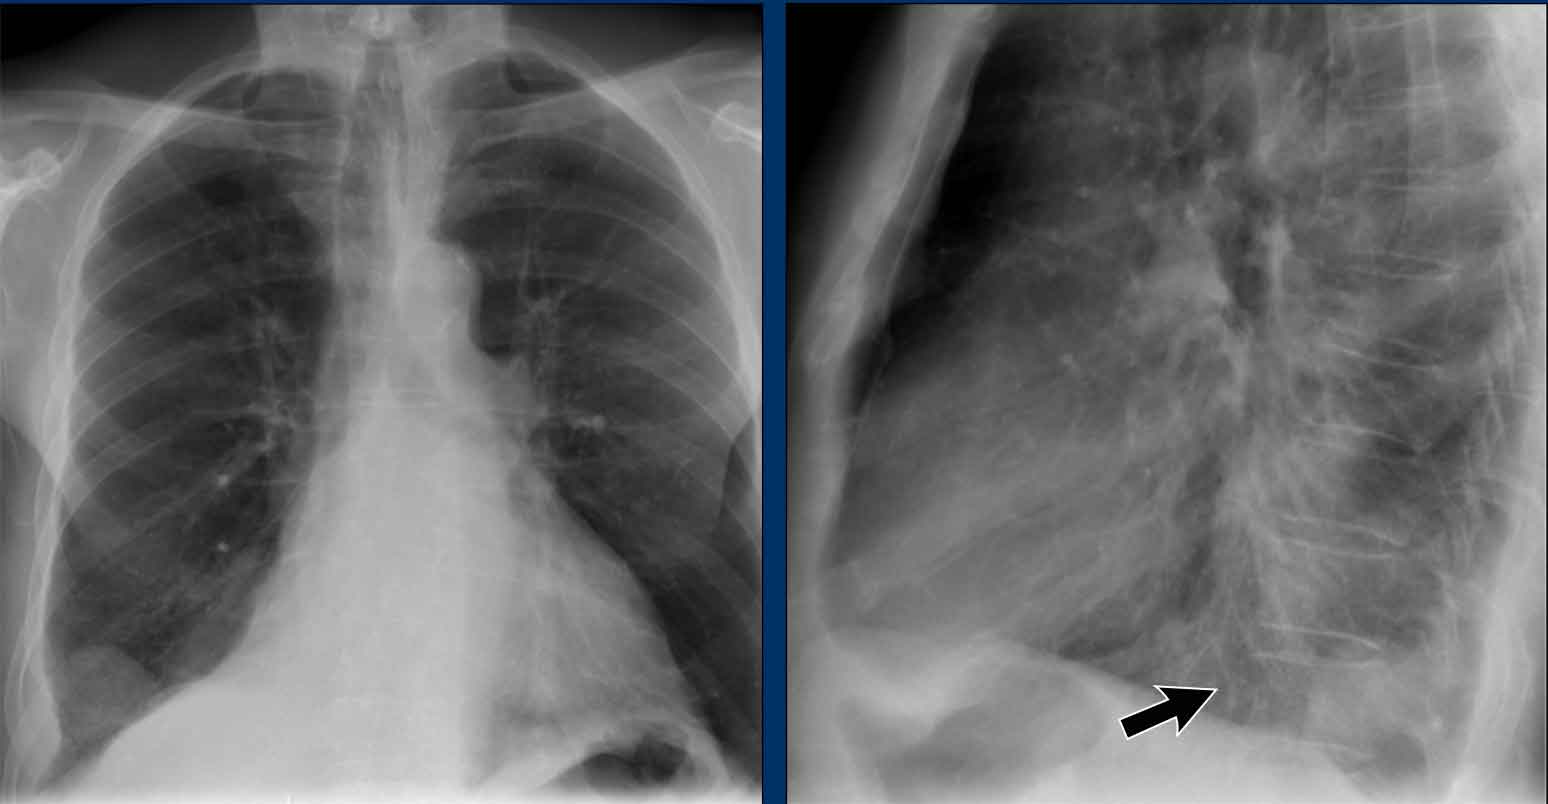

Case Example: Subtle Signs of Congestive Heart Failure

Begin by reviewing these current chest radiographs.

Based solely on these images, one might suspect congestive heart failure (CHF), though the findings are subtle.

Now review the previous study…

Scrolling between the current and prior films significantly increases diagnostic confidence in your diagnosis of congestive heart failure.

Key comparative findings include:

- Cardiac size: Slightly increased compared to the previous study; however, cardiomegaly was already present.

- Pulmonary vasculature: Mild vascular engorgement suggesting elevated pulmonary venous pressure.

- Interstitial markings: Subtle signs of interstitial edema .

- Pleural effusions: Bilateral small effusions, with subtle changes in the inferoposterior borders of the lower lobes, suggesting fluid accumulation.